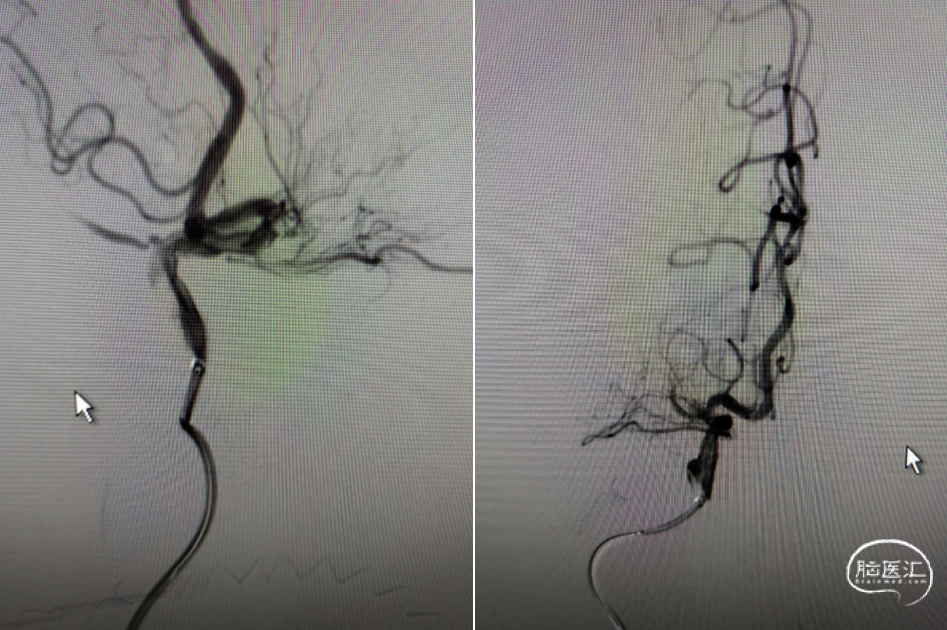

术后正位造影。

术后侧位造影

(术后8h CT)右侧放射冠区、右侧基底节区、右侧额叶多发急性梗死。

(术后7d CT)右侧放射冠区、右侧基底节区、右侧颞叶、额叶多发急性梗死。

(术后14d CTA)RMCA-M1支架植入术后改变。

2022年6月23日:左上肢肌力2+级;左下肢肌力5-级;可流利行走;言语欠流利;神志清楚;NIHSS 5分;mRS 2分。